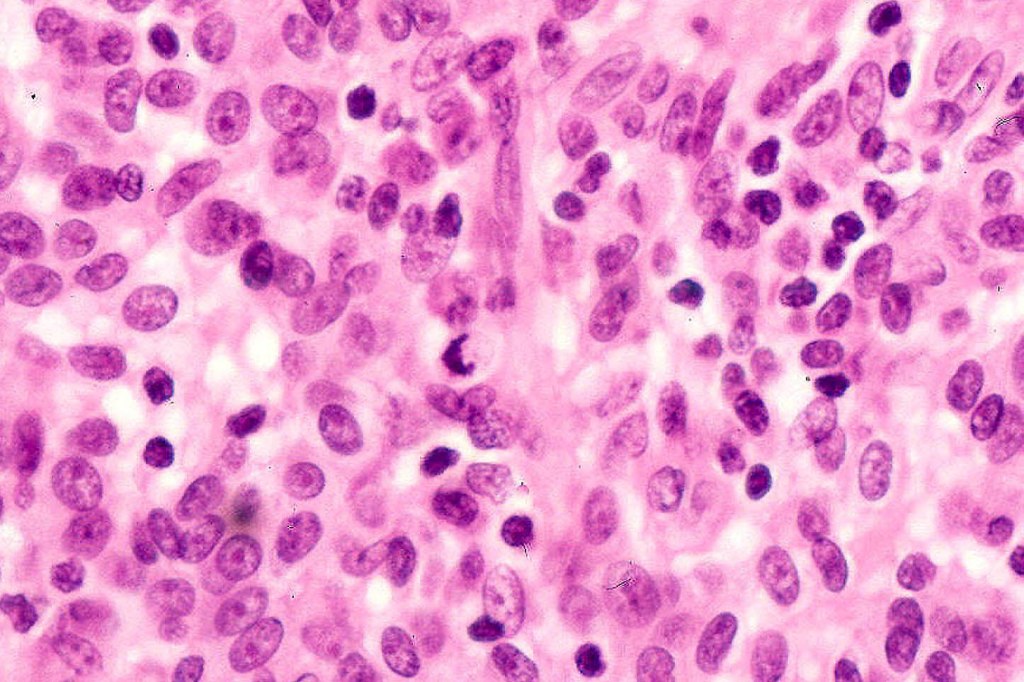

•Usually compound nevus with intense infiltration by lymphocytes, histiocytes and occasional plasma cells, in particularly florrid examples immunohistchemistry may be necessary to identify the nevus cells

•CD8+ve>CD4+

•CD20 +ve to a much minor extent

•Nevus cells often show degenerative atypia (nuclear pleomorphism, hyperchomatism & sometimes fine granular pigmentation (gray or gray/green)

•Melanophages present particularly in older lesions

•Mitoses can be seen in the lymphocytes but not the nevus cells